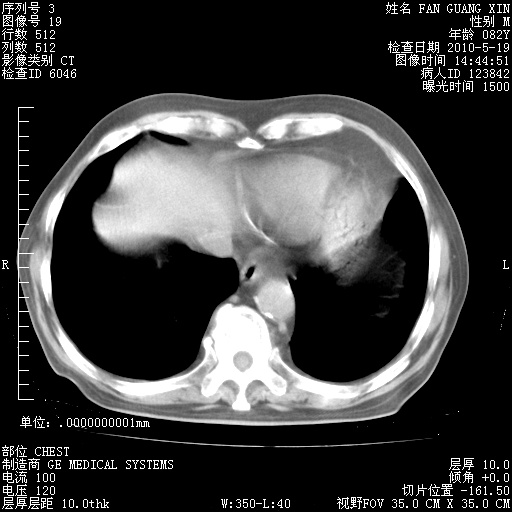

可改为口服强的松40-50mg/d治疗,若病情仍稳定,胸部阴影不再吸收可逐渐减量